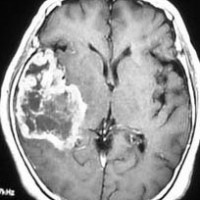

典型的な膠芽腫のガドリニウム増強画像です。右の側頭葉から発生したために目立った症状が無く,この大きさで発症しました。何となくボッとしていると言うのが訴えでした。腫瘍の周囲がガドリニウムで白く増強されて,内部は壊死で低信号(黒っぽい)になっています。